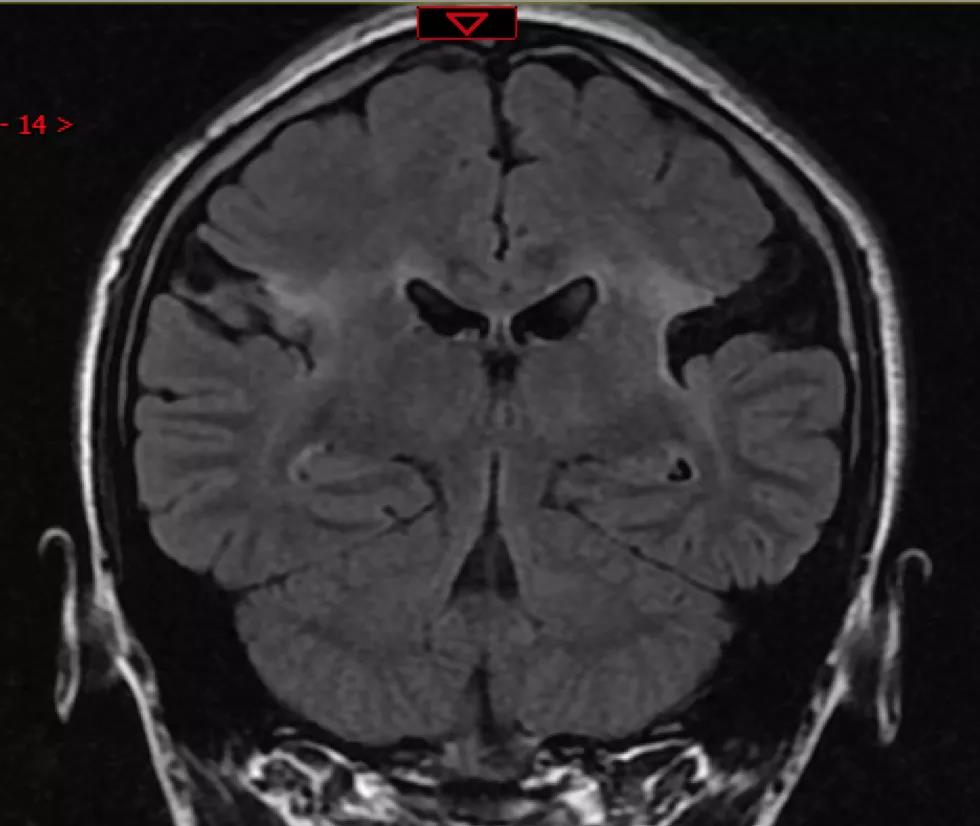

今年5月初,小梁出现一次大发作,发作持续的时间比以前要长,到联勤保障部队第904医院癫痫外科就诊。待病情稳定后,胡医生给她做了相关检查,脑电图提示双侧中央区不同步棘波、尖波、棘-慢波、尖-慢波表现。头颅核磁共振提示,双侧中央区软化灶改变。脑电图和核磁共振的结果都表明,小梁的癫痫发作不能通过常规手术解决。